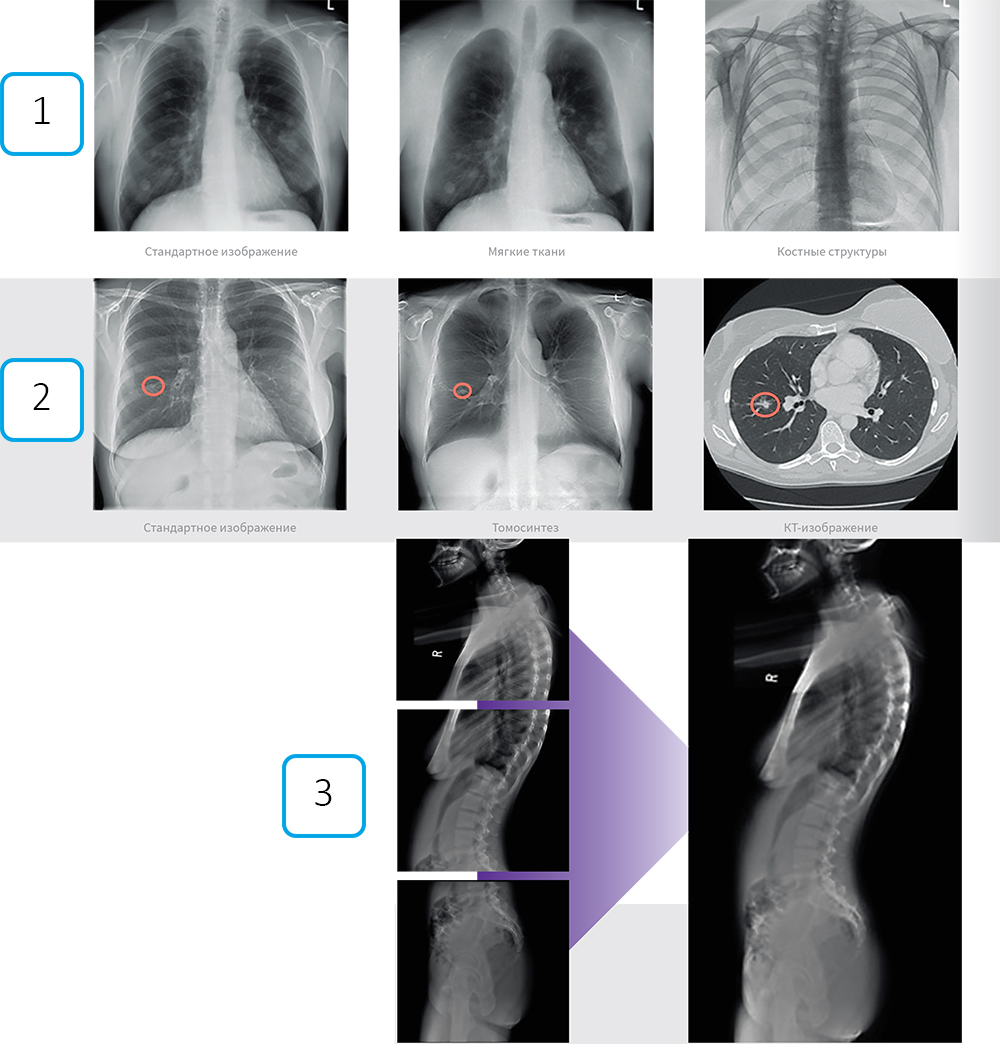

- Томосинтез

Аппарат за один проход делает серию низкодозовых снимков (до 60 кадров) с разных углов. Программа создаёт из них послойные срезы исследуемой области. Технология устраняет эффект наложения органов, что особенно полезно при обследовании легких и молочных желез, снижая необходимость в дополнительных КТ-исследованиях.